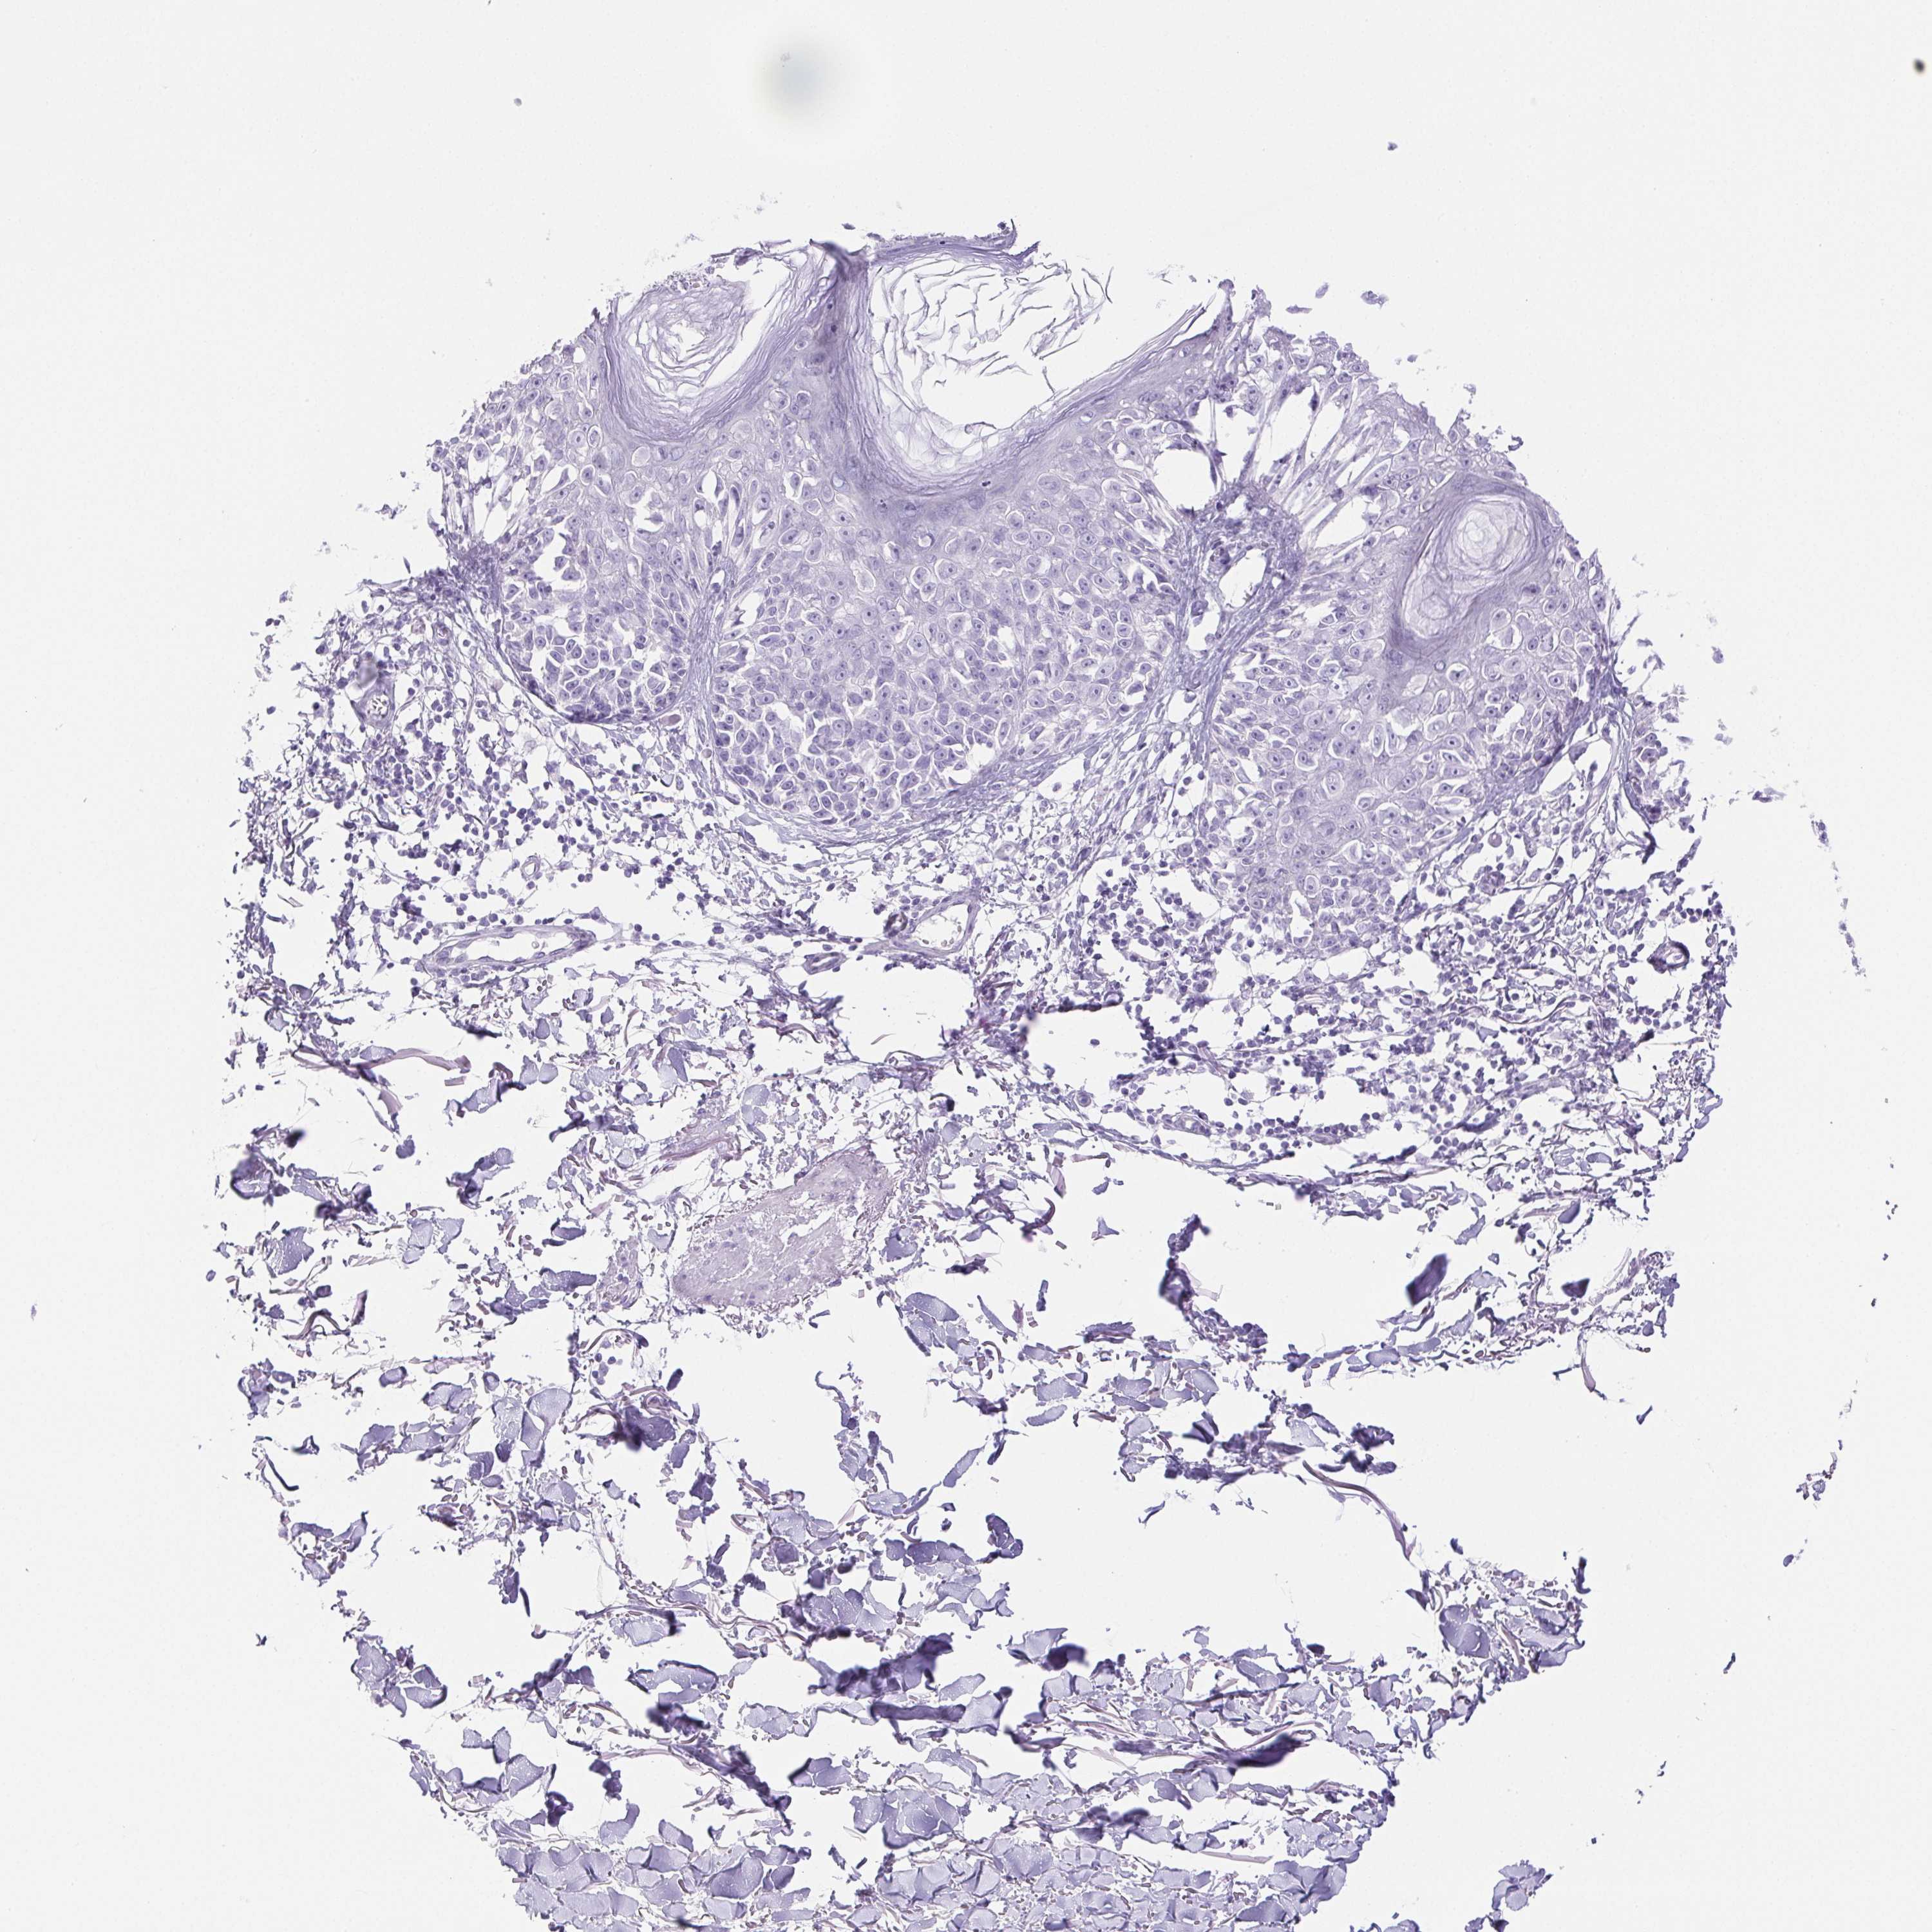

MELANOMA - Protein expressioni

A mouse-over function shows sample information and annotation data. Click on an image to view it in a full screen mode. Samples can be filtered based on level of antibody staining by selecting one or several of the following categories: high, medium, low and not detected. The assay and annotation is described here.

Note that samples used for immunohistochemistry by the Human Protein Atlas do not correspond to samples in the TCGA dataset.

Antibody stainingi

Antibody staining in the annotated cell types in the current human tissue is reported as not detected, low, medium, or high, based on conventional immunohistochemistry profiling in selected tissues. This score is based on the combination of the staining intensity and fraction of stained cells.

Each image is clickable and will lead to virtual microscopy that enables deeper exploration of all samples and also displays staining intensity scores, fraction scores and subcellular localization as well as patient and tissue information for each sample.

Antibody CAB016158

Staining

High

Medium

Low

Not detected

Intensity

Strong

Moderate

Weak

Negative

Quantity

>75%

75%-25%

<25%

None

Location

Nuclear

Cytoplasmic/membranous

Cytoplasmic/membranous,nuclear

Malignant melanoma, Metastatic site

Malignant melanoma, NOS